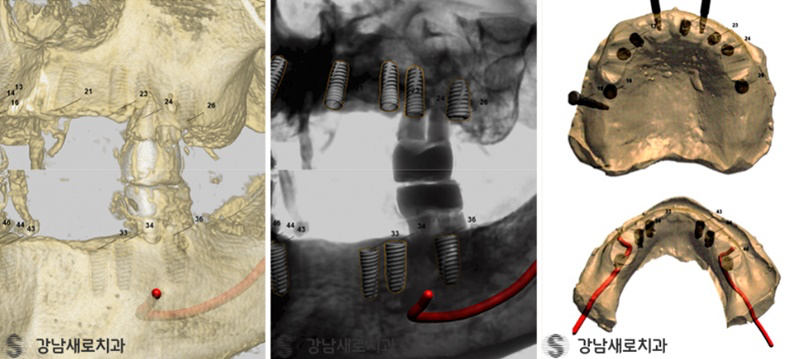

이러한 주기적으로 발생하는 문제들을

해결하기 위해 최신식 3D 장비를 활용해서

수술 당시에 오차를 확실히 줄일 수 있도록

효율적인 방법을 사용하고 있었는데요.

따라서 통증에 대한 사람들의

공포감을 감소시킬 수 있었으며,

사람 개개인의 구강 상태나 잇몸 건강 및

잇몸뼈의 구조가 다 다르며 위와 같은 차이를

파악하여 더욱 꼼꼼한 제작을 해야 했는데,